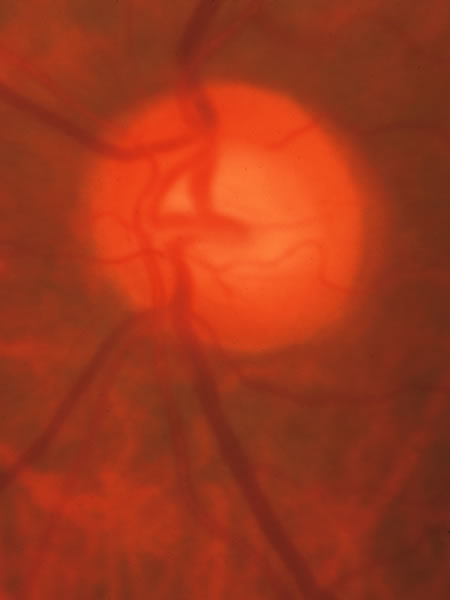

Fig. 37. Swollen optic nerve superiorly during anterior ischemic optic neuropathy caused by giant cell arteritis.

Fig. 38. Same eye after resolution of the attack, with excavation extending to the superior rim of the disc, mimicking the appearance of glaucomatous cupping.